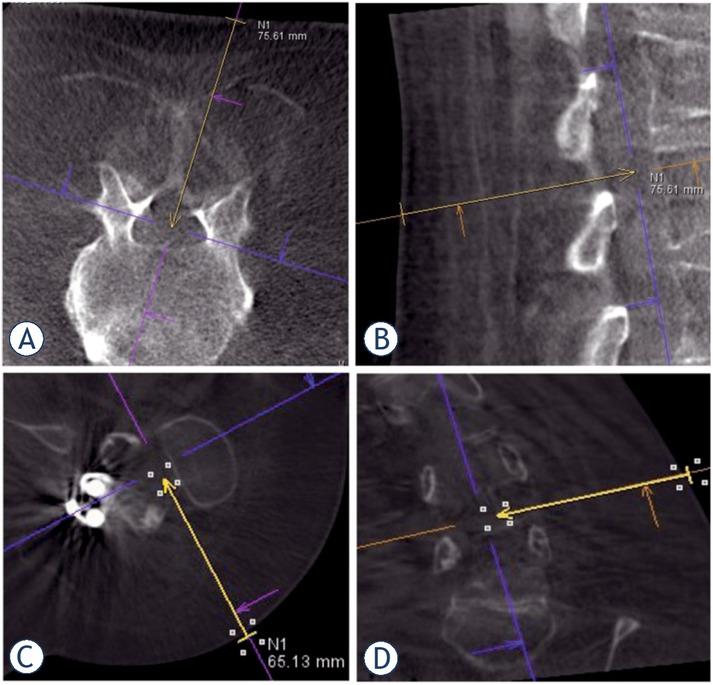

Figure 1